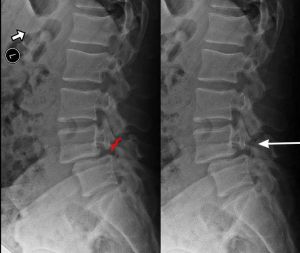

When we look at the spine from the side, we can imagine a scotty dog. It is outlined above. The pars fracture is seen as a collar around the dog's neck. Instability and movement can cause the neck to widen. We will see this below in an X-ray example.

X-RAY SHOWING A PARS FRACTURE DEFECT

THE WHITE OUTLINE SHOWS THE SLIPPAGE.